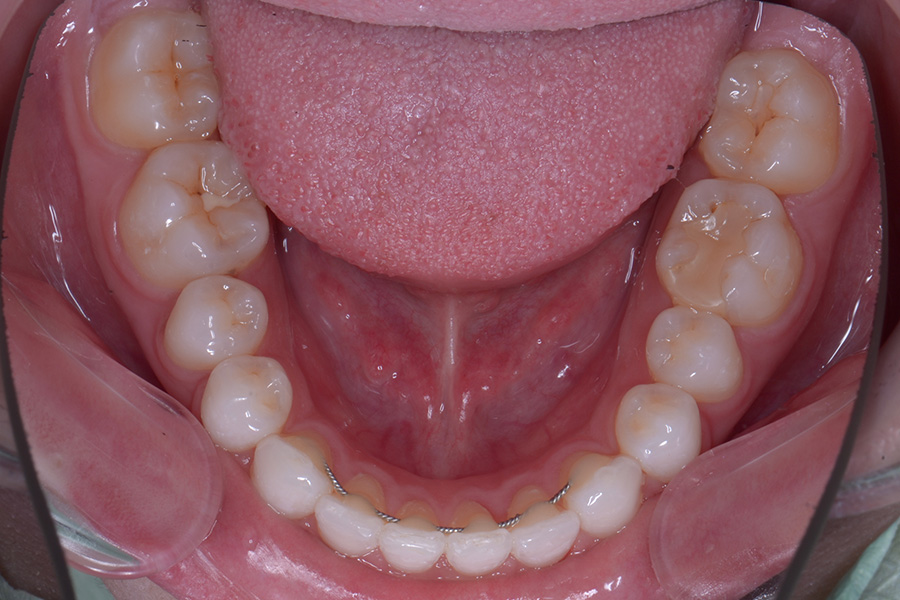

治療前

治療後

主訴 前歯のすきっ歯と捻じれを治したい

治療内容 上下顎ラビアル矯正(表側矯正)